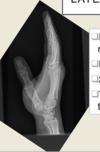

Q

Gout